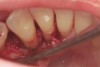

Fig. 18  Subgingival calculus and severe bone loss.

Figure 18

The patient had been referred for an implant consultation for the mandibular right canine. She had very deep probing depths on the lingual. When the flap was raised, a significant amount of subgingival calculus was seen as a local risk factor (Figure 18). However, she had no significant pathology to remove from the situation. Debridement was performed the same as in Case 3 with the rotary ultrasonic and manual instrumentation.

The defect was obturated with mineralized freeze-dried bone and hydrated with platelet-derived growth factor. As with any growth factor, when implementing it clinically, all growth factors require a carrier to bring that growth factor to the desired site, which do not elicit an inflammatory response. In this situation, it is the mineralized freeze-dried bone allograft. This combination was demonstrated by Rosen et al8 to be efficacious in treating intrabony defects. A biologic approach was taken both in terms of the graft and membrane (Figure 19). Primary closure was achieved.